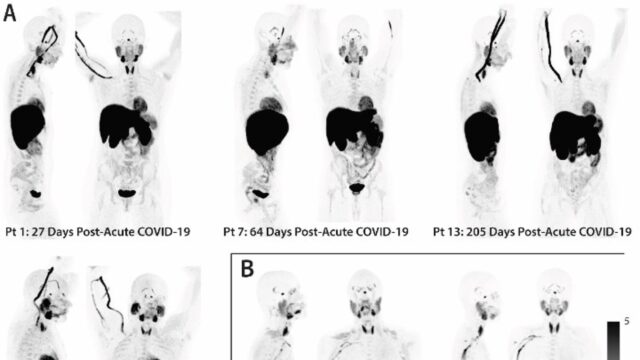

Στη συγκεκριμένη έρευνα συμμετείχαν 24 άτομα που υποβλήθηκαν σε τομογραφία PET σε όλο το σώμα τους. Οι συμμετέχοντες είχαν νοσήσει με Covid-19 από 27 έως 910 ημέρες πριν από την έρευνα. Όπως διαπιστώθηκε, οι ασθενείς που ανάρρωσαν παρουσίαζαν έντονα σημάδια ενεργοποιημένων Τ κυττάρων στο εγκεφαλικό στέλεχος, τον νωτιαίο μυελό, τους ιστούς της καρδιάς και των πνευμόνων και πολλά άλλα σημεία του σώματος. Επιπλέον, αυτή η ενεργοποίηση των κυττάρων συσχετίστηκε με τα μακροχρόνια συμπτώματα Covid. Για παράδειγμα, τα άτομα που ανέφεραν επίμονα προβλήματα στους πνεύμονες παρουσίαζαν ισχυρότερα σημάδια ανοσολογικής ενεργοποίησης στους πνεύμονες.